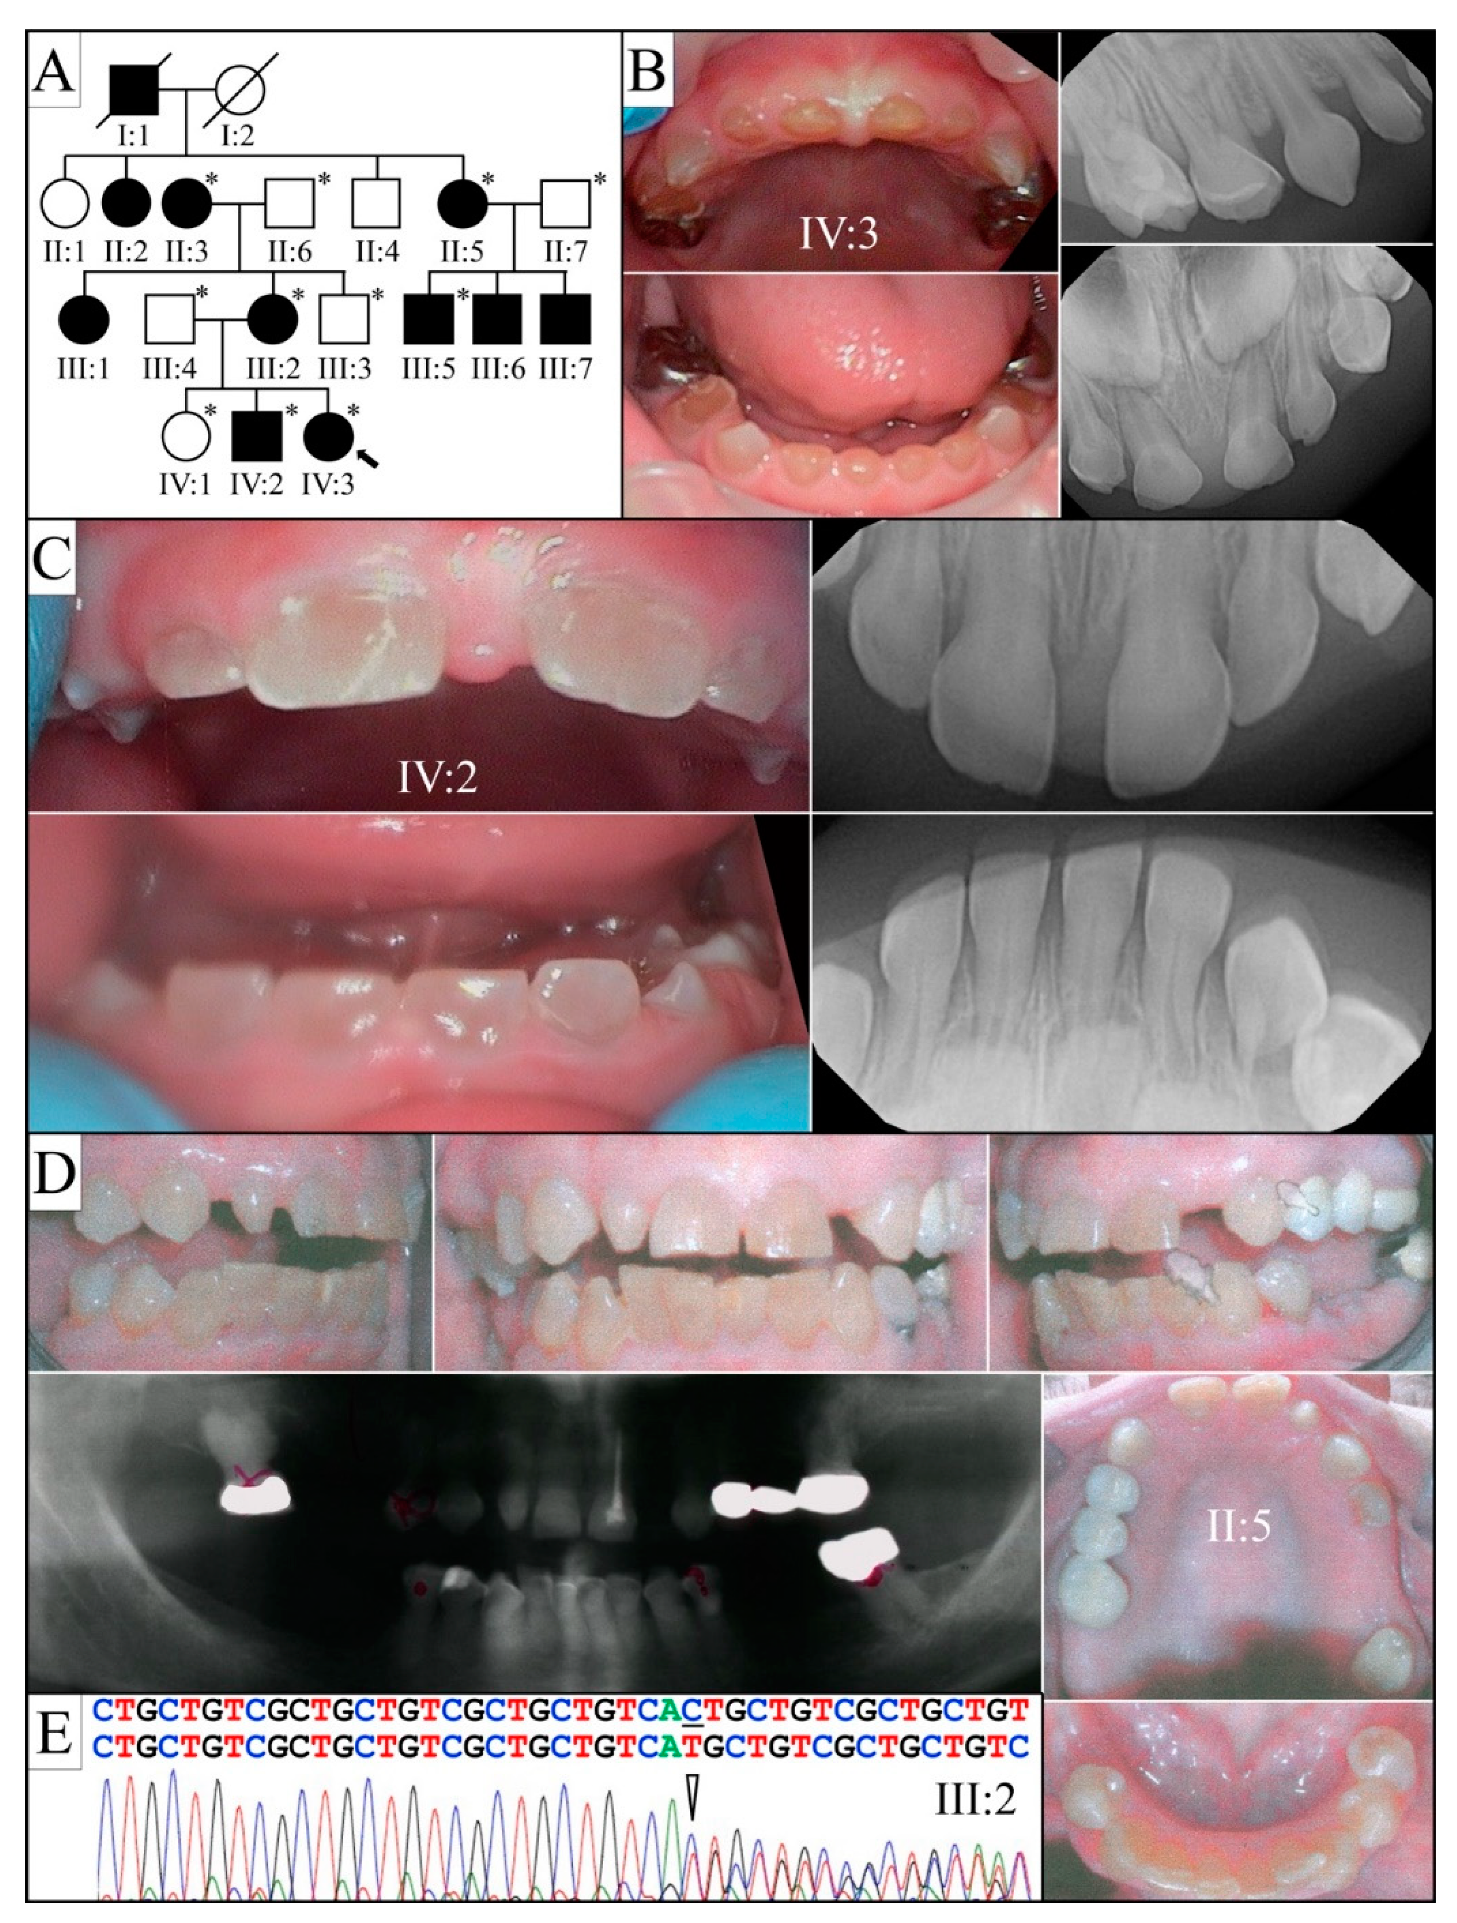

3.2. Four Families with DGI-III: 5′ DSPP Mutations

3.3. Eight Families with 3′ DSPP Mutations Causing DD-II or DGI-II